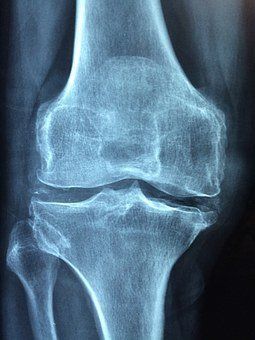

- Überwärmte, geschwollene und steife Gelenke am Morgen